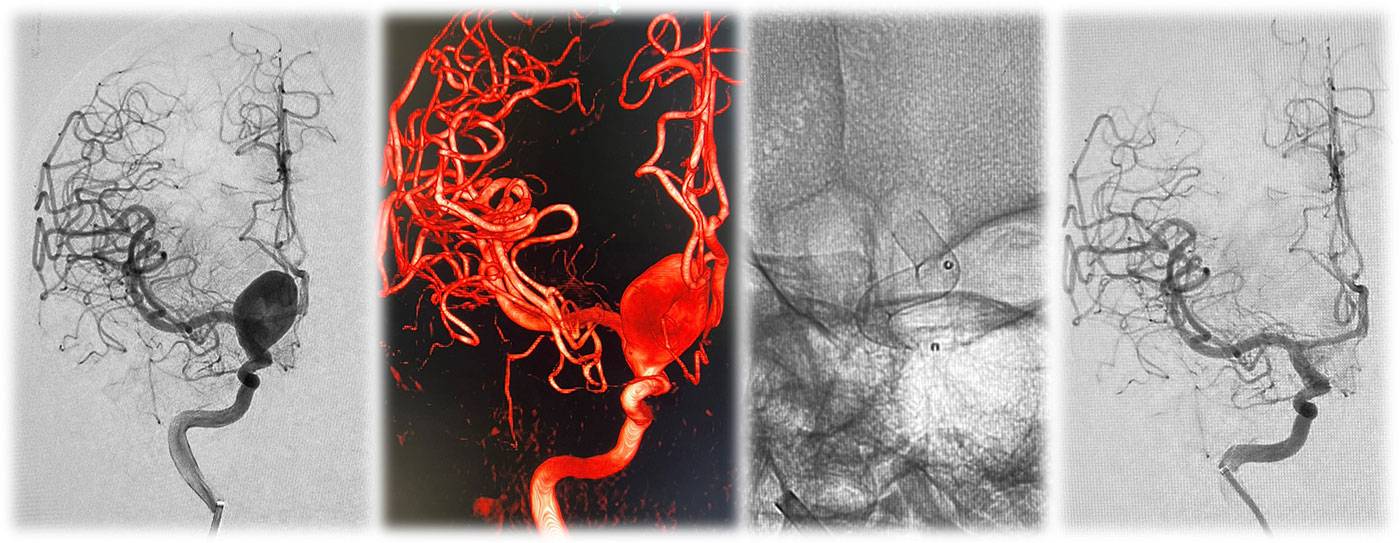

A 5-year-old male child presented with complaints of recurrent generalized tonic–clonic seizures and right-sided weakness ,predominantly involving the lower limb along with anger outbursts and abnormal behaviour.